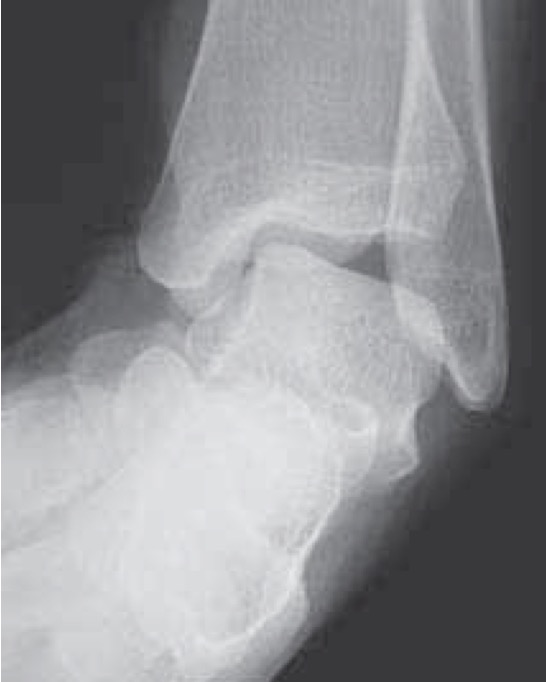

Xrays

Osteochondral lesions

Loose bodies

Stress Xrays

![]() |

ATFL tear

CFL tear